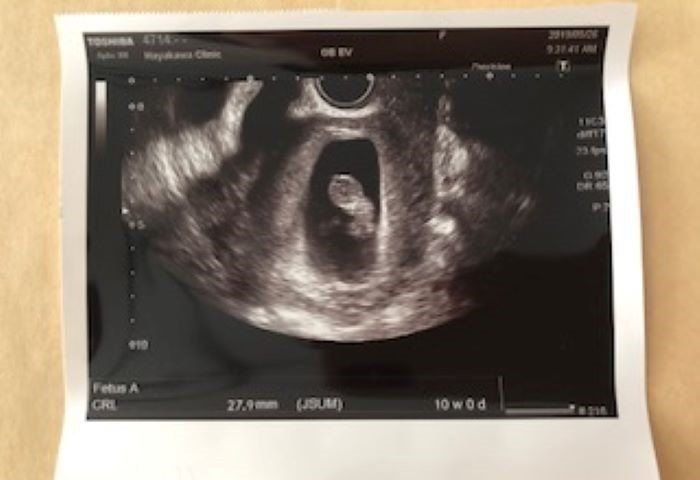

妊娠10週 危機をのりこえすくすくと成長中

10w1d D:27.9mm

妊娠10週、退院直前のエコー写真です。切迫流産の危機からひとまず脱することができ、この危機をともに乗り越えてくれた赤ちゃんに「よく頑張ったね。えらいよ!」と声を掛けました。その日からしばらくの間、張り止めを飲んで引き続き経過観察をすることになりました。